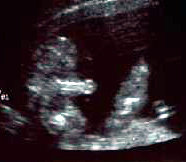

الأسبوع ال18